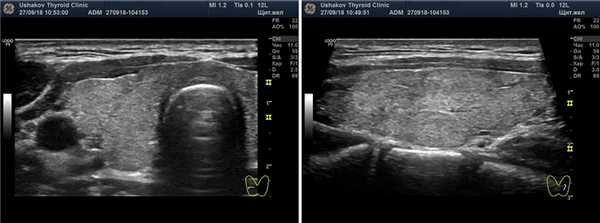

Рисунок 3. Разные настройки режима ЭДК ультразвукового допплеровского исследования. Представлена одна и та же проекция правой доли щитовидной железы. Период между снимками ― 1 минута. Слева ― с нормальными базовыми настройками (смотрите справа значения PRF), справа ― с настройками более высокой чувствительности. Видно, что при изменении настроек определяется не нормальный, а усиленный кровоток.